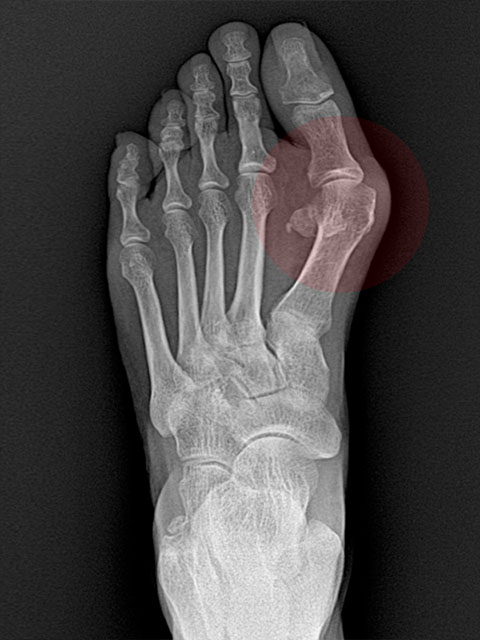

• Before

엄지발가락이 둘째 발가락 쪽으로 심하게 휘어 관절의 탈구가 우려되는 단계

• After

심하게 꺾였던 엄지발가락의 각도가 수술 후 일자로 교정된 상태